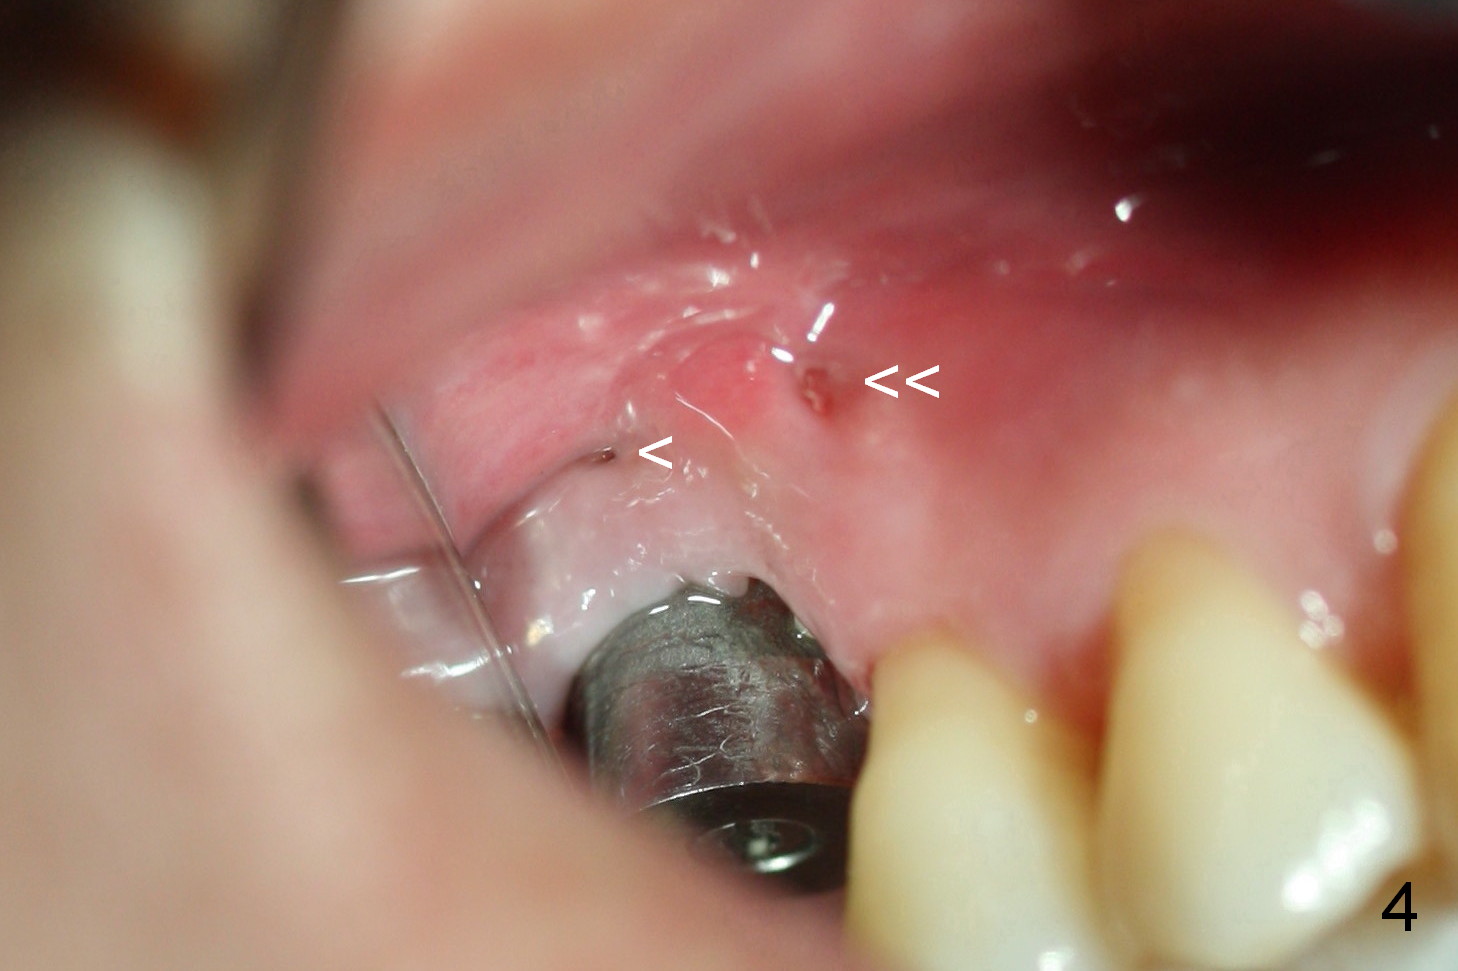

The patient returns for follow up 2 and 4 weeks postop. Two weeks postop, the fistula closes after removal of perio dressing. Mesial to the healing fistula is a small wound opening, from which bone graft granule are exposed. The Osteotape is partially exposed from the gingival margin. Four weeks postop, the osteotape is not visible from the recessed gingival margin (Fig.4). The fistula remains close (single arrowhead: <)), whereas the small wound opening mentioned above has closed (double arrowheads: <<). Gingival graft should have been done with GBR to decrease the chance of gingival recession. A second GBR appears necessary.